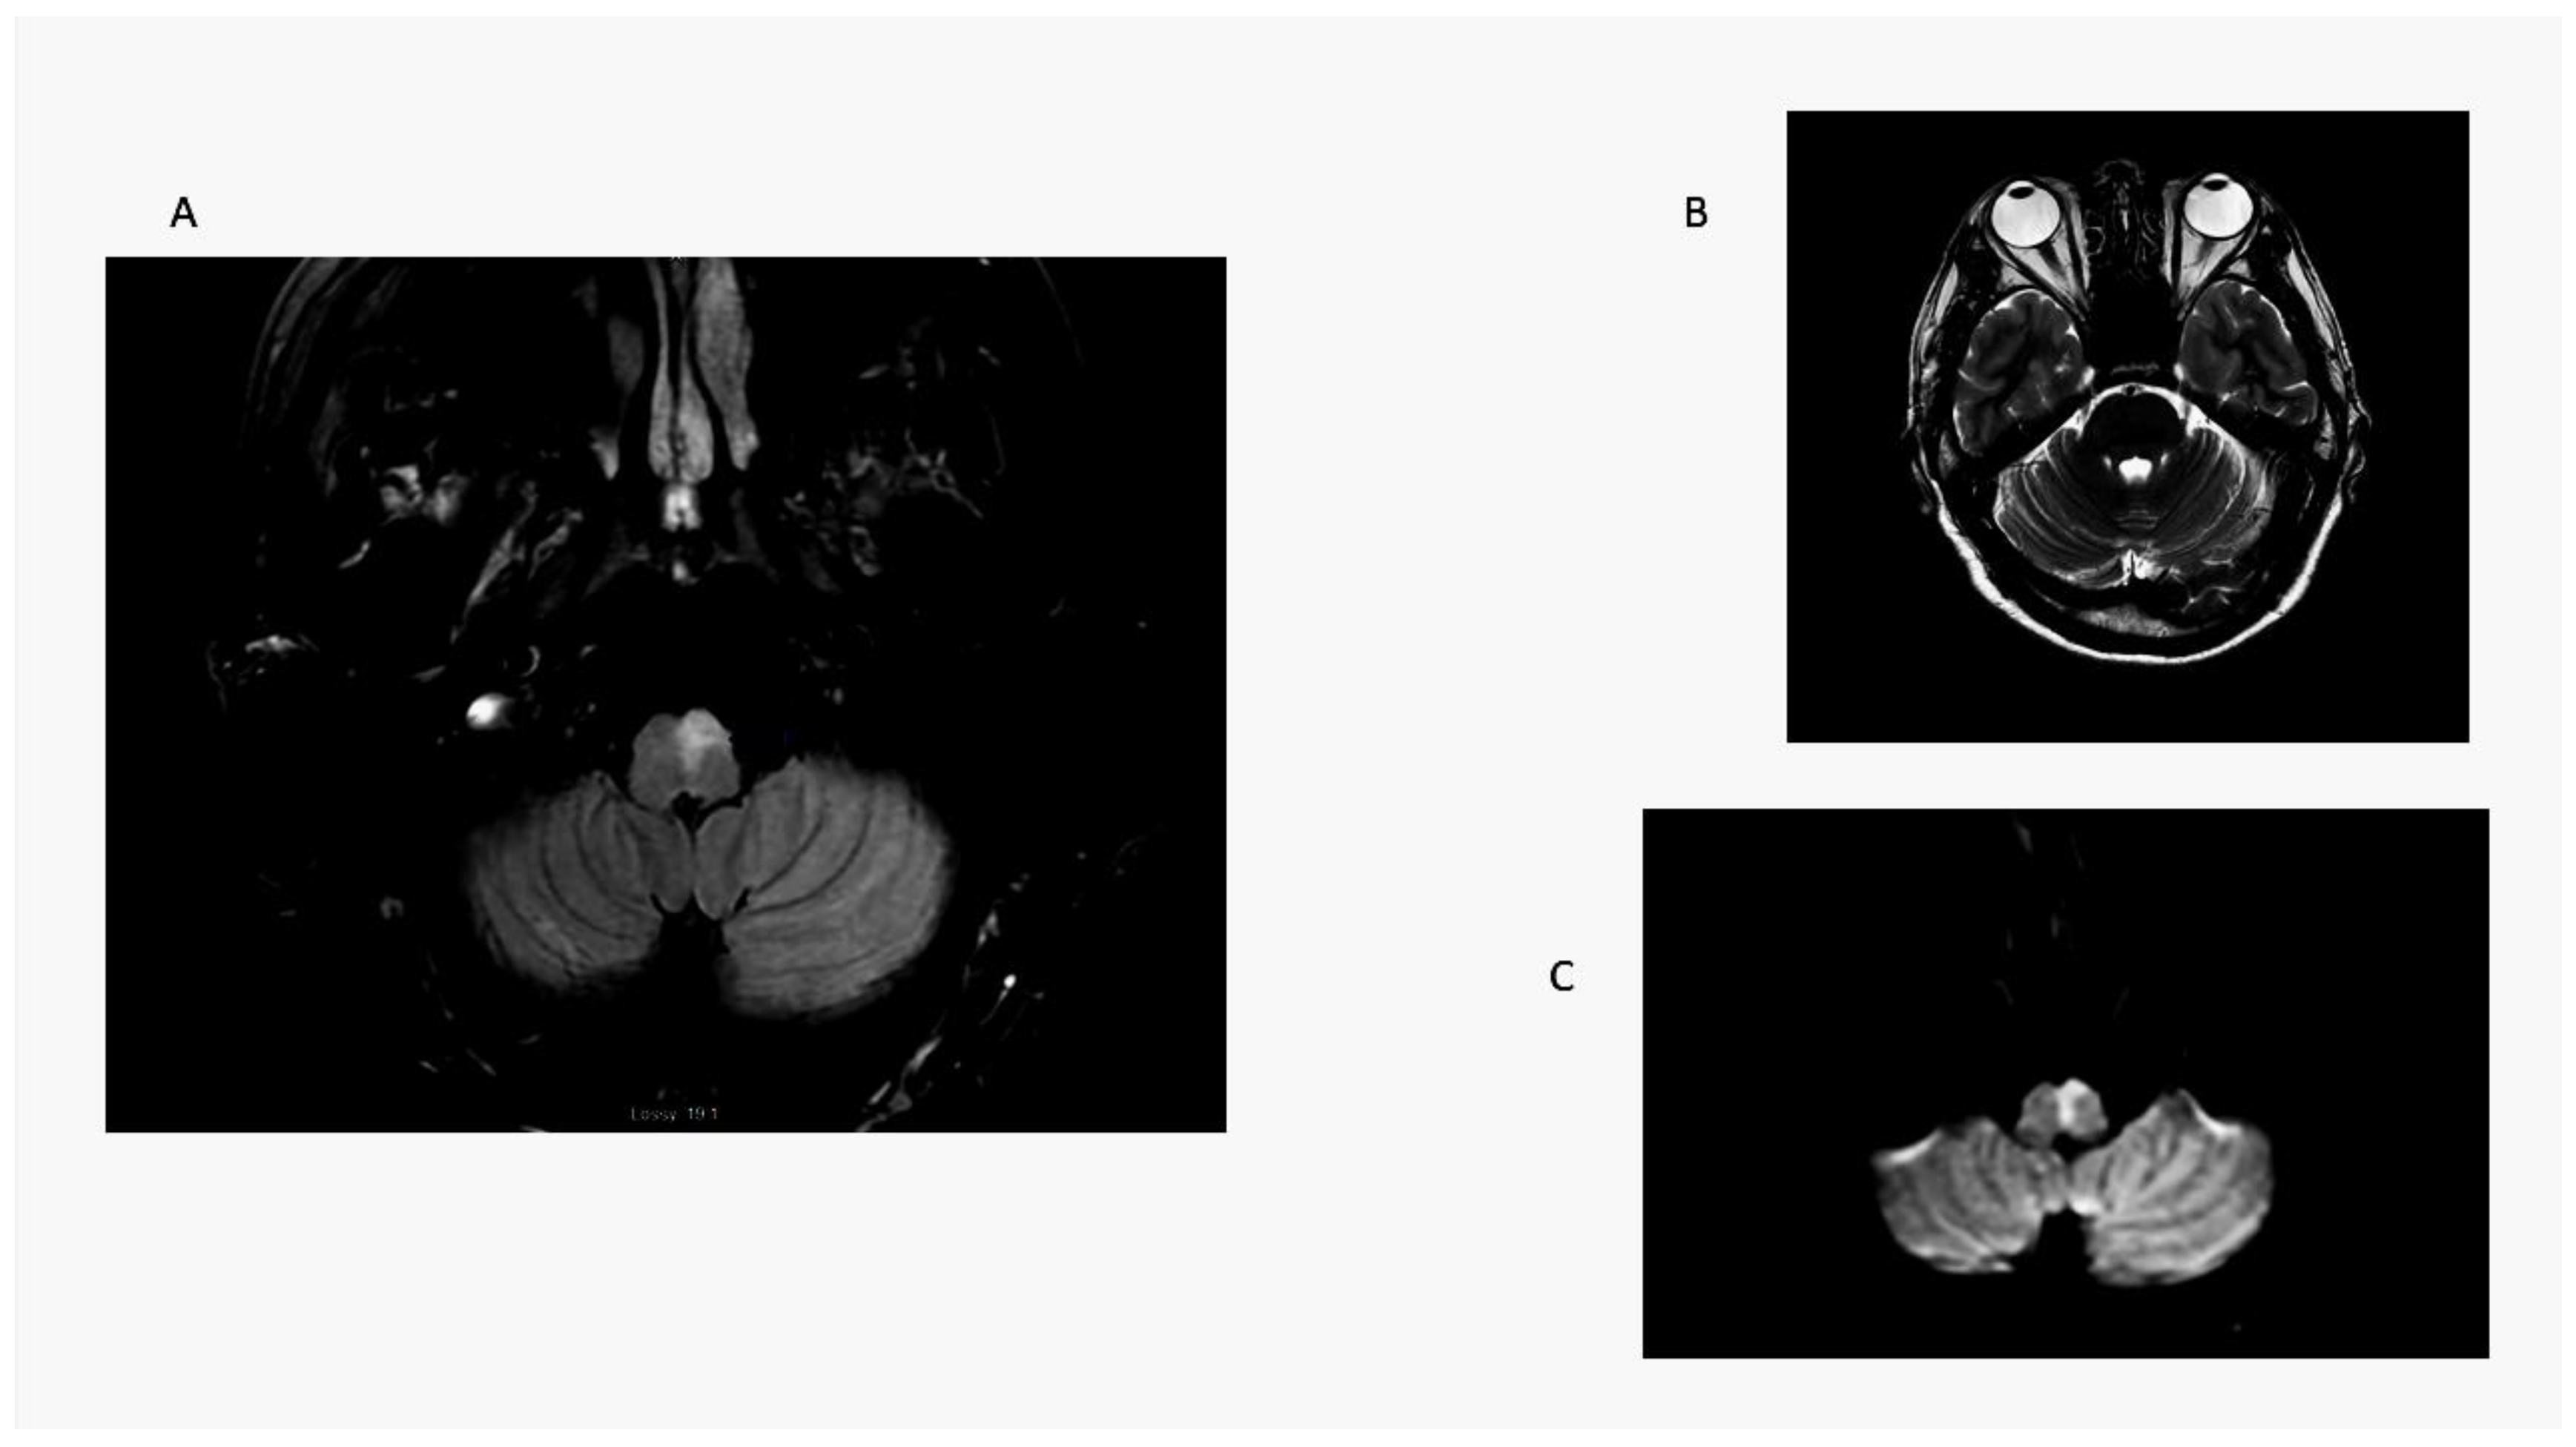

Unlike LMS patients, the one medial medullary stroke (MMS) patient in this series had contralesional truncal ataxia and hemiparesis; he did not have OLD. He was not able to sit at the bedside and could not stand with a wide base initially (ataxia grade 3) (Figure 4). In a previous series, radiographic ocular deviation occurred in MMS and correlated with an ipsilesional horizontal nystagmus slow phase rather than OLD in one patient [37]. An earlier large series of MMS patients did not include OLD testing [38].

Figure 4.

Medial medullary stroke. Panel (A): axial T2 MRI shows an elongated paramedian area of hyperintensity involving the left medullary pyramid and extending toward the dorsal medulla near the floor of the fourth ventricle. Note absence of radiographic ocular deviation in a T2 axial MRI (Panel (B)). Panel (C) is a DWI scan showing restricted diffusion confirmed by ADC map. Here, a combination of right-sided weakness and grade 3 ataxia causes contralesional falls.